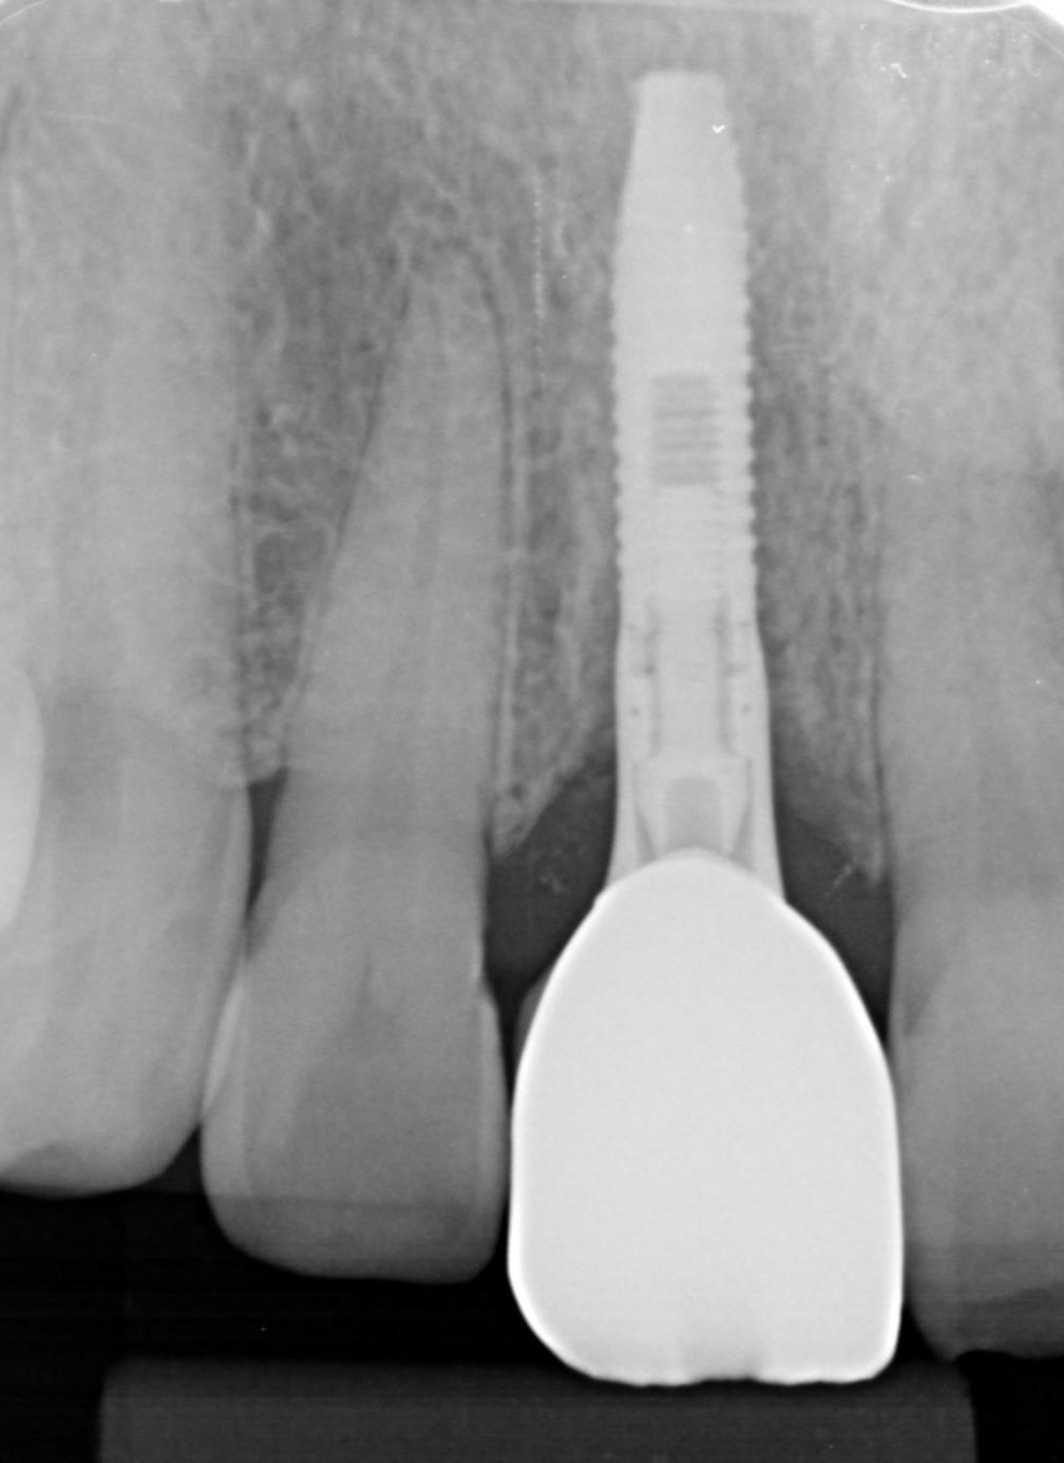

このレントゲン写真のように理想的な位置にインプラントが設置できます。